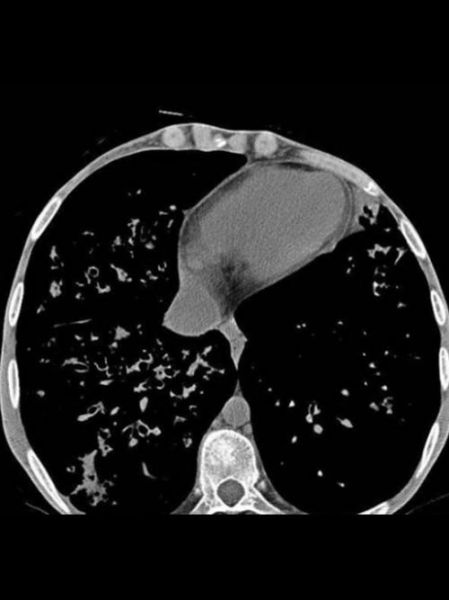

囊性纤维化(Cystic Fibrosis,CF)是一种常染色体隐性遗传病,由CFTR基因突变导致氯离子通道功能障碍,进而引发多系统黏液堵塞。患者最常问的两个问题是:“囊性纤维化能治好吗?”以及“现在有哪些最新治疗进展?”下面分板块拆解。

(图片来源网络,侵删)